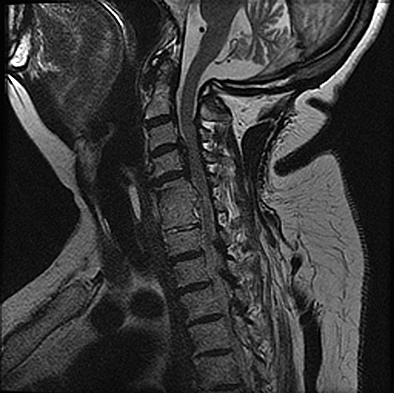

Figures 1 and 2 show sagittal and axial MRI from an 83-year-old woman with an ataxic gait, loss of dexterity, and intermittent loss of bowel and bladder control. The symptoms have been getting progressively worse over the past several weeks.

4. Pigmented villonodular synovitis Discussion: B

The patient has a pannus at the C1-2 articulation that is compressing the spinal cord and causing myelopathy symptoms. The development of a pannus at this location has been associated with rheumatoid arthritis. Steinberger and associates showed increased morbidity and mortality when using an anterior approach and the surgery took longer than 4 hours. Chieng and associates showed better outcomes and lower complications rates using a posterior approach.

Question 12 of 100

Discussion: A